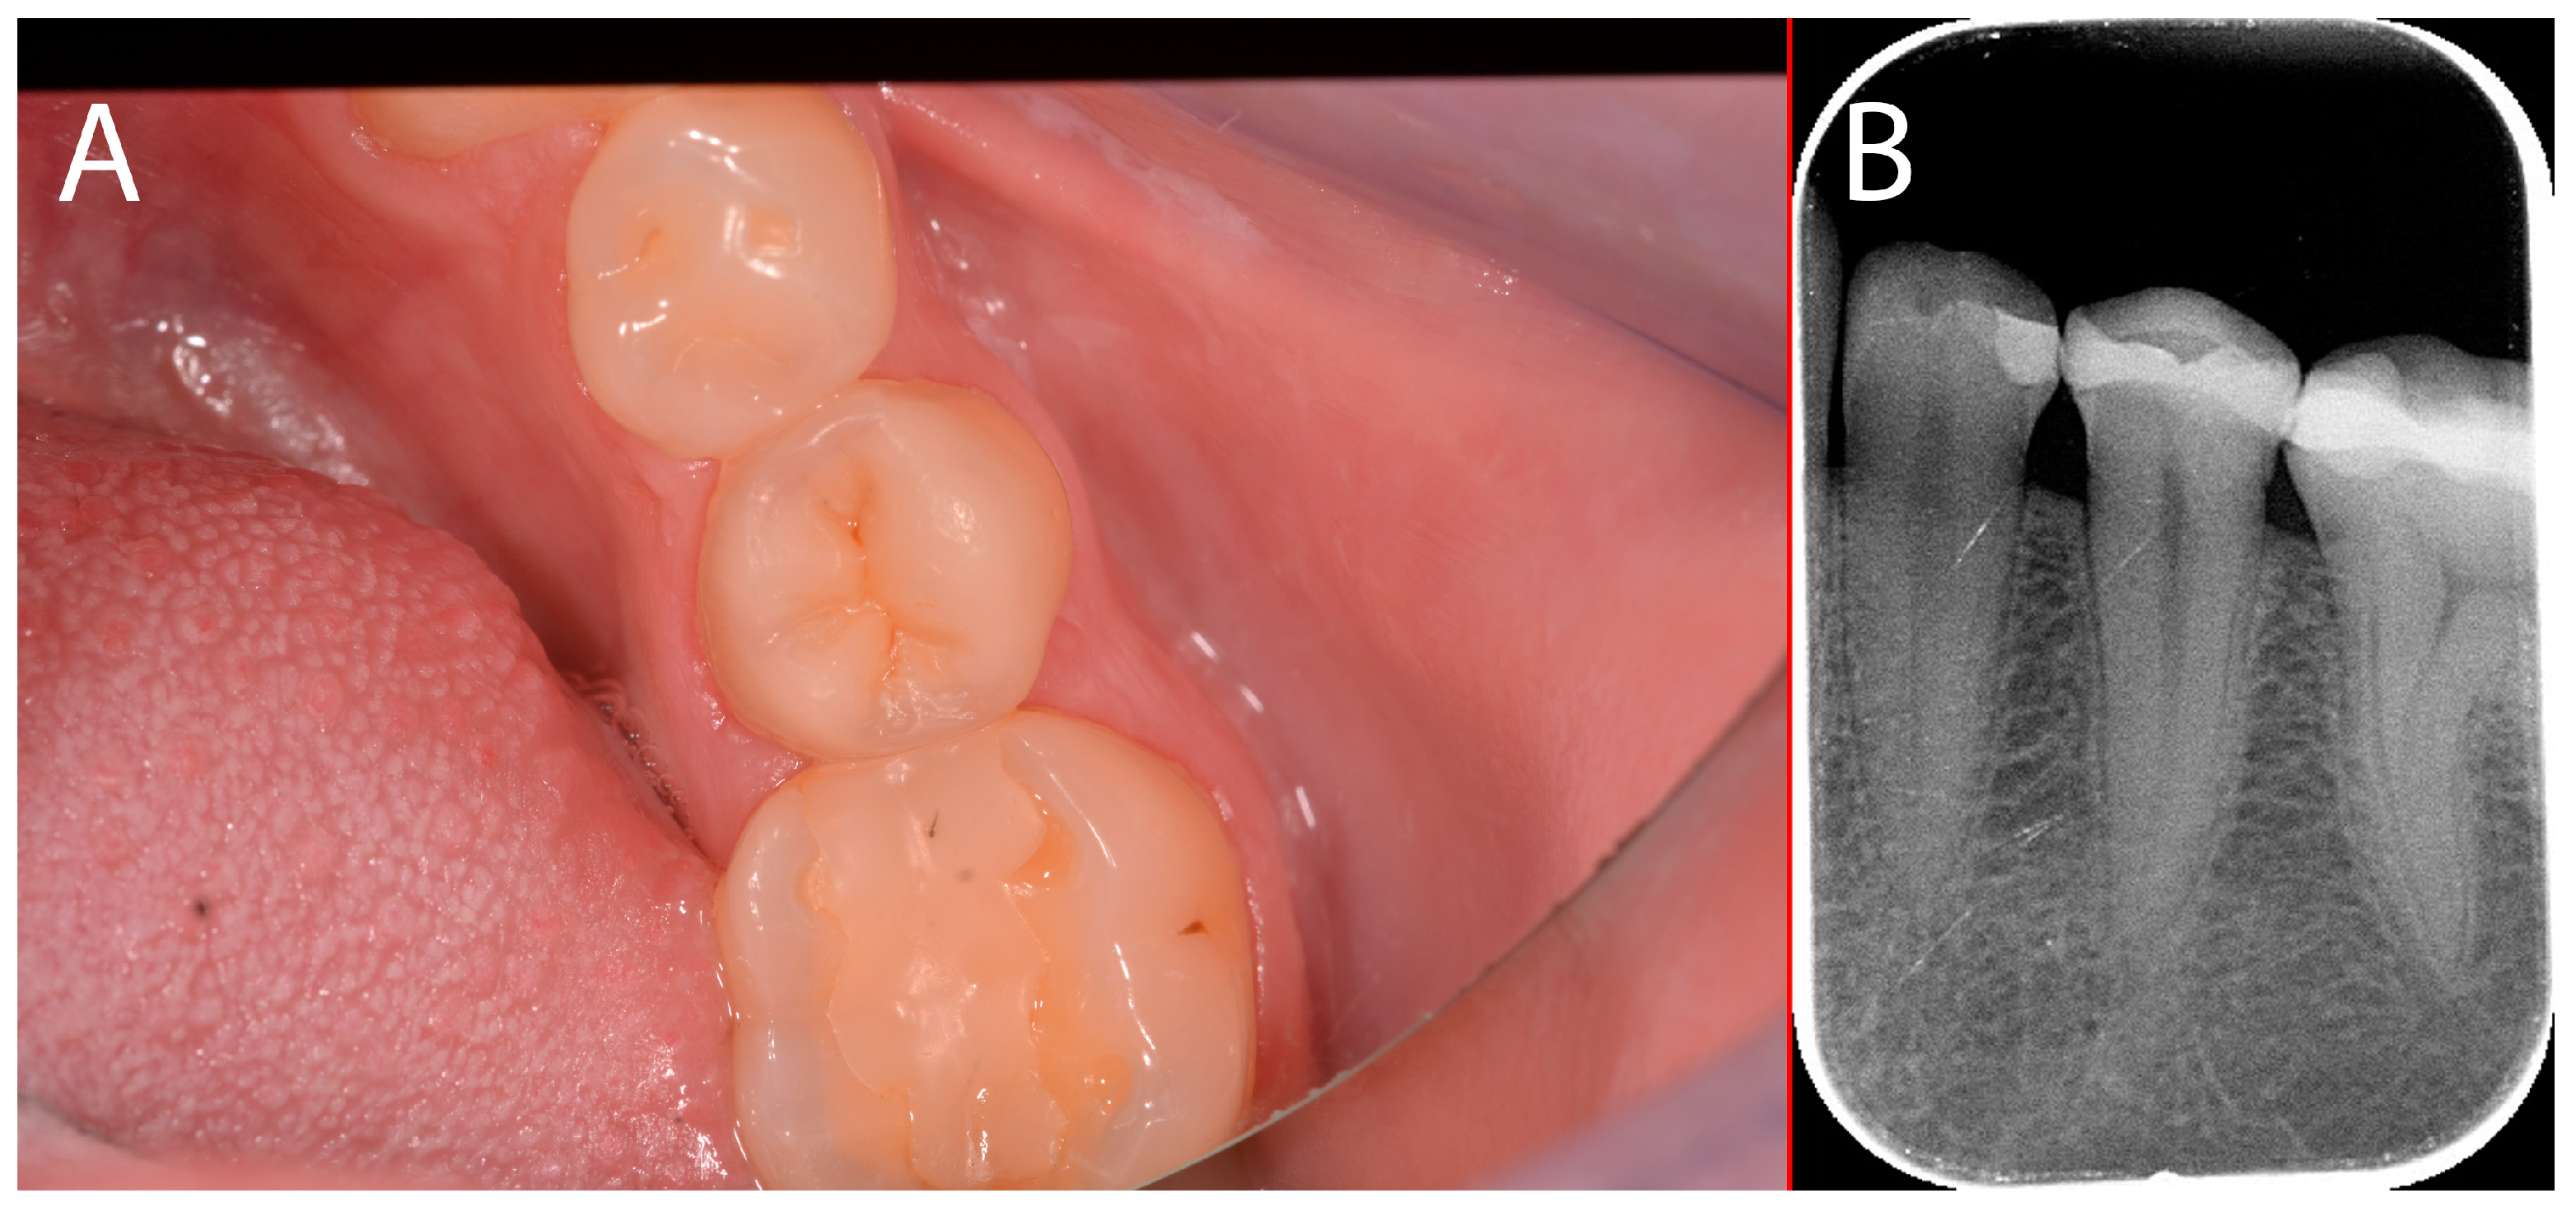

2.4. Case Presentation #3

2.4.1. Anamnesis, Physical Examination

2.4.2. Treatment